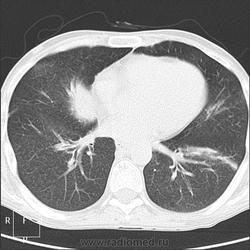

Прозрачность обеих легких равномерно неинтенсивно снижена за счет наличия множественных, плохо дифференцируемых мелкоочаговых теней, сливающихся между собой и расположенных главным образом во внутренних отделах легких, ближе к корням легких, образуя картину «бабочки». Сосудистый рисунок диффузно усилен, в виде радиальных извитых теней за счет перибронхиальной и периваскулярной инфильтрации. Линейные тени пластинчатых ателектазов. Корни легких малоструктурны. Органы средостения не смещены. Сердечная тень не увеличена."

Я не вижу "Бабочку", а Вы?

Из-за почечной недостаточности контрастирования не будет. Такая картина в легких мне впервые попадается. Есть несколько вариантов, но очень хочется услышать мнения коллег! Какие будут мысли?

Тут воды полно, саму печень надо поискать, я постаралась поиграть окнами, чтоб её было видно. Не особо и увеличена. Уже.

Возможно, что проблемы с печенью давно - общий белок, холестерин низкий, асцит (есть здесь изменения в печени?, опыта интрпретации КТ у меня нет) на фоне печёночной недостаточности - страдают почки. Отёки скорей всего за счёт низкого белка, сердечная недостаточность наверное тоже есть. В лёгких - похоже пневмосклеротические изменения, мерещатся признаки лёгочной гипертензии (корни "обрубленные" какие-то).

Печень по цвету (плотности) должна быть почти такой же, как и селезенка (50-70 единиц), а в данном случае 10 единиц, вода в брюшной полости 5-7 единиц. Так что нормальных гепатоцитов там кот наплакал.

В легких - рентгенограмму я описала как усиление за счет интерстициального компонента. Корень кажется обрубленным: из-за асцита высоко стоит диафрагма, нижние отделы легких поджаты. Пневмосклероза я не вижу. А по КТ не знаю, как интерпретировать: интерстициальный отек, токсический васкулит?

В легких обычное сдавление нижних отделов за счет высокого давления в брюшной полости.

Тогда, учитывая всё вышесказанное, вероятно интерстициальный отёк ( гипопротеинемия, почечная недостаточность, токсическое поражение...)

Интерстициальный отек легких. Хронический калькулезный панкреатит. Киста хвоста поджелудочной железы, без биопсии уверенно раковое перерождение не исключить. Киста сальниковой сумки /вероятно тоже панкреатического генеза/. Жировой гепатоз печени с портальным циррозом /биопсия/. Камень устья? пузырного протока. Геморрагические кисты почек??? Асцит.

Парочка моих шаблонов, наверное первый соответствует настоящему состояниюПрозрачность обеих легких равномерно неинтенсивно снижена за счет наличия множественных, плохо дифференцируемых мелкоочаговых теней, сливающихся между собой и расположенных главным образом во внутренних отделах легких, ближе к корням легких, образуя картину «бабочки». Сосудистый рисунок диффузно усилен, в виде радиальных извитых теней за счет перибронхиальной и периваскулярной инфильтрации. Линейные тени пластинчатых ателектазов. Корни легких малоструктурны. Органы средостения не смещены. Сердечная тень не увеличена.

Прозрачность обеих легких неравномерно, преимущественно в нижних отделах, неинтенсивно снижена за счет наличия множественных, плохо дифференцируемых крупноочаговых теней, сливающихся между собой и расположенных главным образом во внутренних отделах легких, ближе к корням легких, образуя картину «бабочки». В прикорневых и паравертебральных отделах значительное усиление сосудистого рисунка, размытого грубопетлистого, обусловлено венозным полнокровием. Тени венозных сосудов определяются, как поперечно расположенные полосы с нерезкими контурами, преимущественно в нижних отделах. Определяются горизонтальные линии Керли вследствие интерстициального отека междольковых перегородок Корни легких расширены малоструктурны. Органы средостения не смещены. Сердечная тень увеличена в поперечнике, талия сглажена, аорта уплотнена, умеренно развернута

Я не вижу "Бабочку", а Вы?